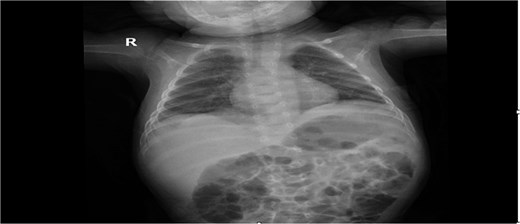

Postoperative recovery was uneventful. Chest radiography showed full re-expansion of the left lung and normalization of the mediastinal position (Fig. 3).

Post-op chest X-ray was normal and show a full expansion of the left lung, with normal diaphragm, normal stomach gas in the intraperitoneal region.